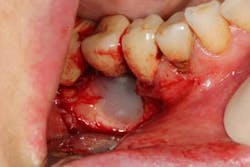

A recent review looked at the Er:YAG laser as a method of detoxifying implant surfaces. (16) This laser has the ability to effectively remove calculus and bacterial colonies from the impregnated implant surface without causing thermal damage to the implant and surrounding tissues. In addition, the ease of use and the focused beam allows access to often unattainable areas on the diseased implant, making a once recommended explanation into a regenerative possibility. The following case report describes the use of the Er:YAG laser for implant surface decontamination and concomitant regenerative therapy to treat an implant with advanced peri-implantitis.

A 52-year-old woman with a noncontributory medical history, taking no medications with no reported food or drug allergies, was referred to my office from a general dentist in order to obtain a second opinion. She had a lower right premolar implant placed in an oral surgery office five years ago that was suffering from severe peri-implantitis. (Fig. 1) Her first dentist told her that the implant had to be removed and that her treatment options were a fixed partial denture in the form of a three-unit bridge or a partial denture because re-implantation was not feasible. In addition, he sent her to a periodontal office that verified his statement, telling the patient that because of nerve proximity and the poor chance of ridge augmentation, re-implantation was unlikely. When she asked if saving the implant was possible, both the dentist and the periodontist told the patient that because of the level of bone loss, regenerative treatment would not work.Fig. 4